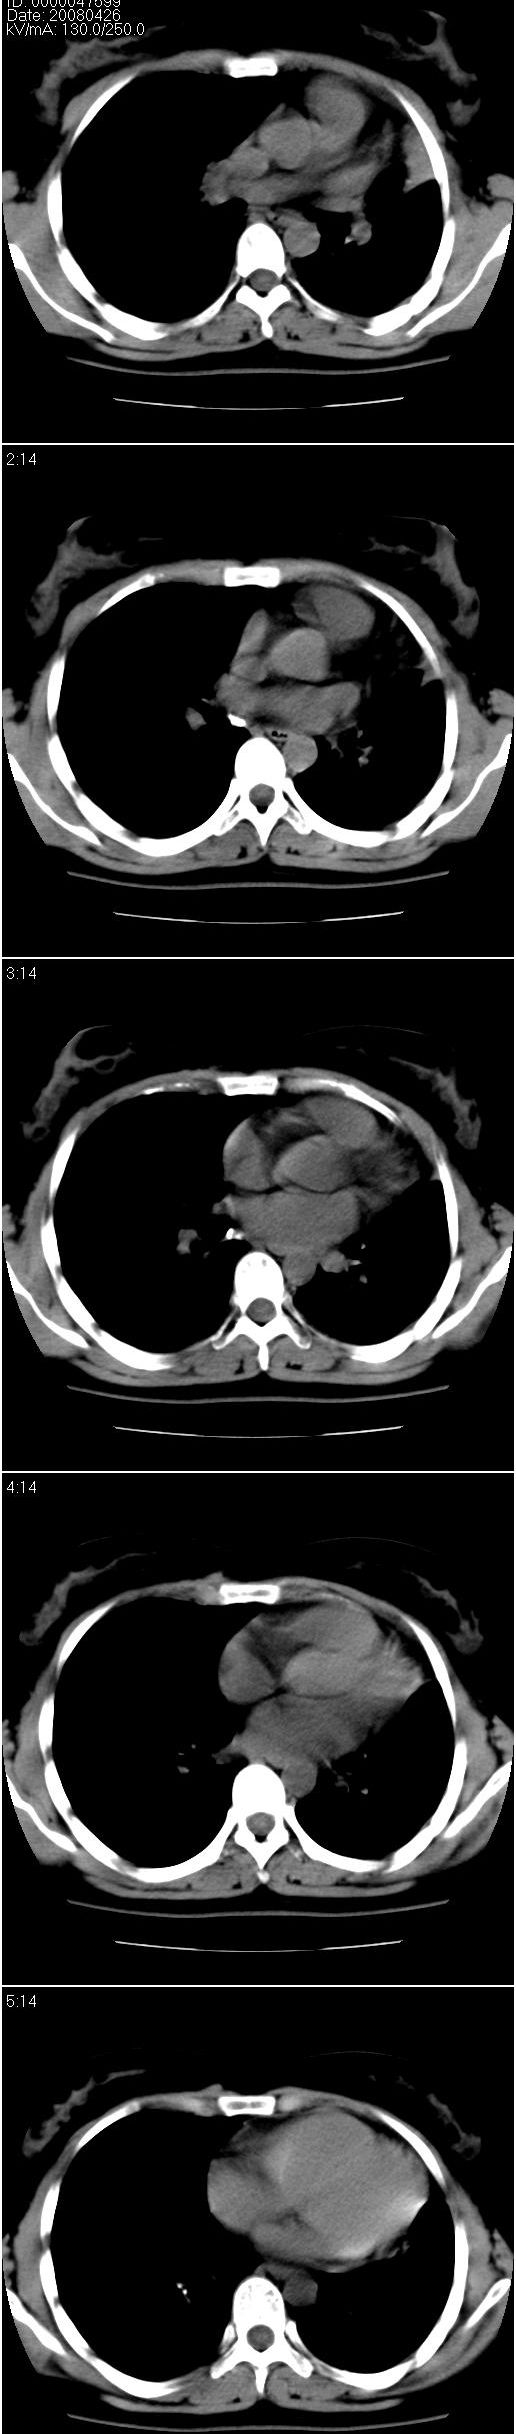

以下是引用光影相伴在2008-4-26 11:32:00的发言:[br]左肺继发性结核伴左肺上叶肺不张。建议:行纤维支气管镜检查排除支气管内膜结核。

以下是引用光影相伴在2008-4-26 11:32:00的发言:[br]左肺继发性结核伴左肺上叶肺不张。建议:行纤维支气管镜检查排除支气管内膜结核。

以下是引用zsl6918在2008-4-26 16:18:00的发言:[br]符合支气管内膜结核的诊断。

以下是引用光影相伴在2008-4-26 11:32:00的发言:[br]左肺继发性结核伴左肺上叶肺不张。建议:行纤维支气管镜检查排除支气管内膜结核。

以下是引用有风的日子在2008-4-26 13:54:00的发言:[br][quote]以下是引用光影相伴在2008-4-26 11:32:00的发言:[br]左肺继发性结核伴左肺上叶肺不张。建议:行纤维支气管镜检查排除支气管内膜结核。